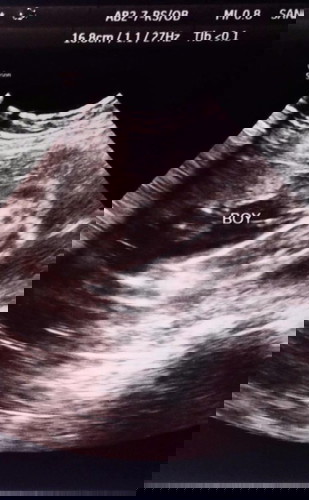

Baby's Gender

Mga mommies,sure na po kaya na boy ito?sabi kasi ni ob/sono di pa daw sure kung boy talaga.25 weeks ako nung nagpa-ultrasound.Unisex daw muna bilhin ko para kay baby.Baka lang may kapareho na result sa inyo. Thanks!😉#1stimemom